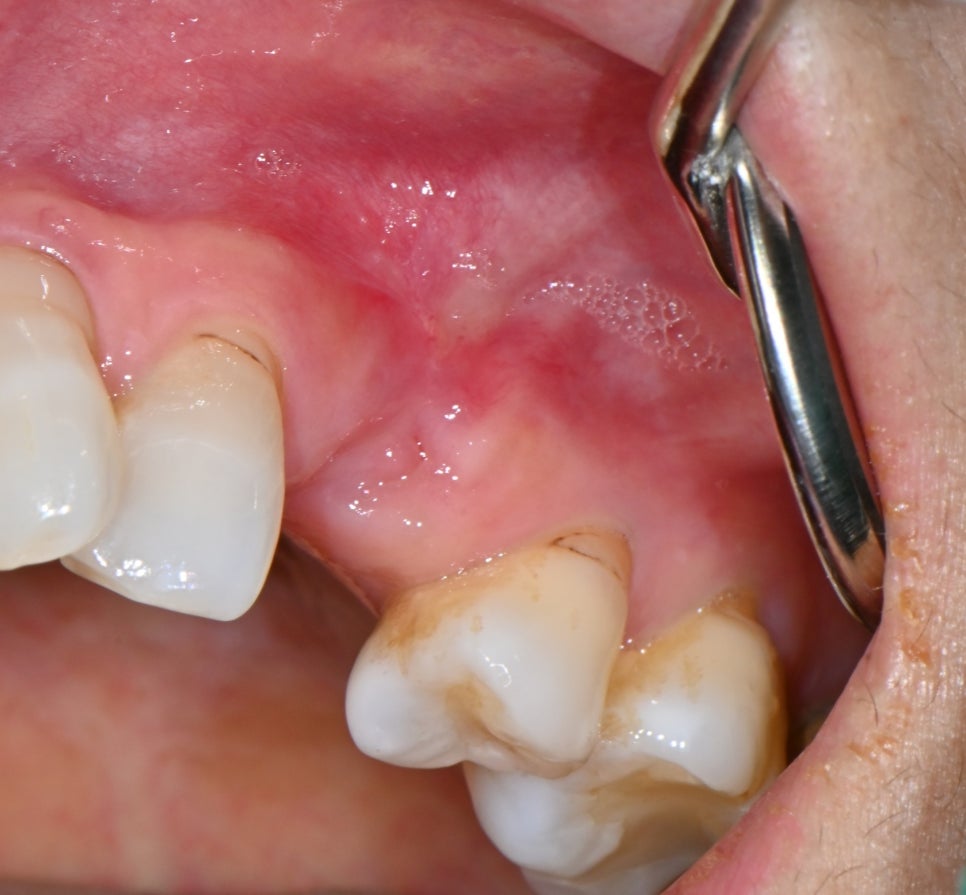

📸 염증이 사라진 상태

골수염(Osteomyelitis) 치료 완료 사진

안쪽까지 염증이 완전히 가라앉은 걸 확인한 후,

정확한 위치에 임플란트를 식립할 수 있었습니다.